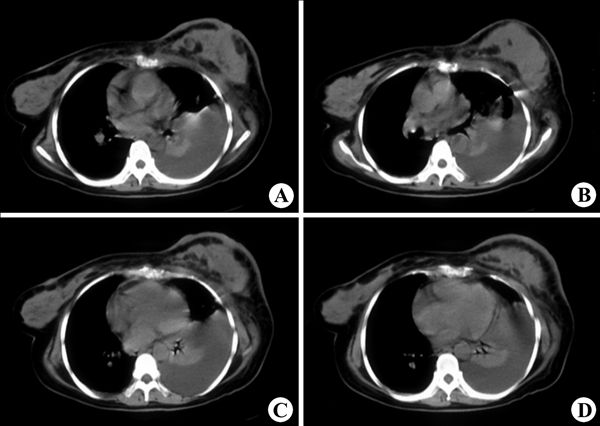

左侧乳腺癌3

影像表现:CT平扫(A~D)示左侧乳房体积明显增大,内可见软组织肿块影,密度欠均匀,有多个小圆形低密度影,邻近胸壁界面相对稍增厚,左侧胸腔大量积液,右乳腺内肿块,为转移所致。

影像诊断:左侧乳腺癌3.